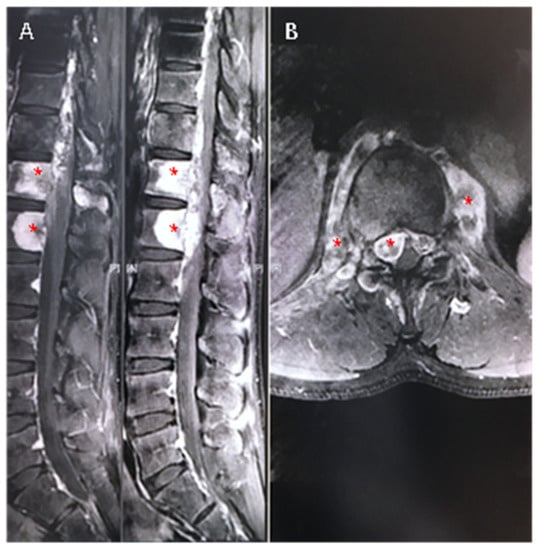

2. Case Report